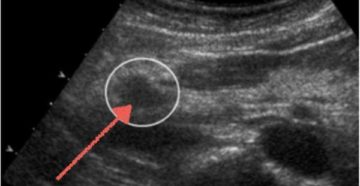

Эхогенность – что это такое и при каких болезнях изменяются эхографические признаки Для выявления заболеваний…